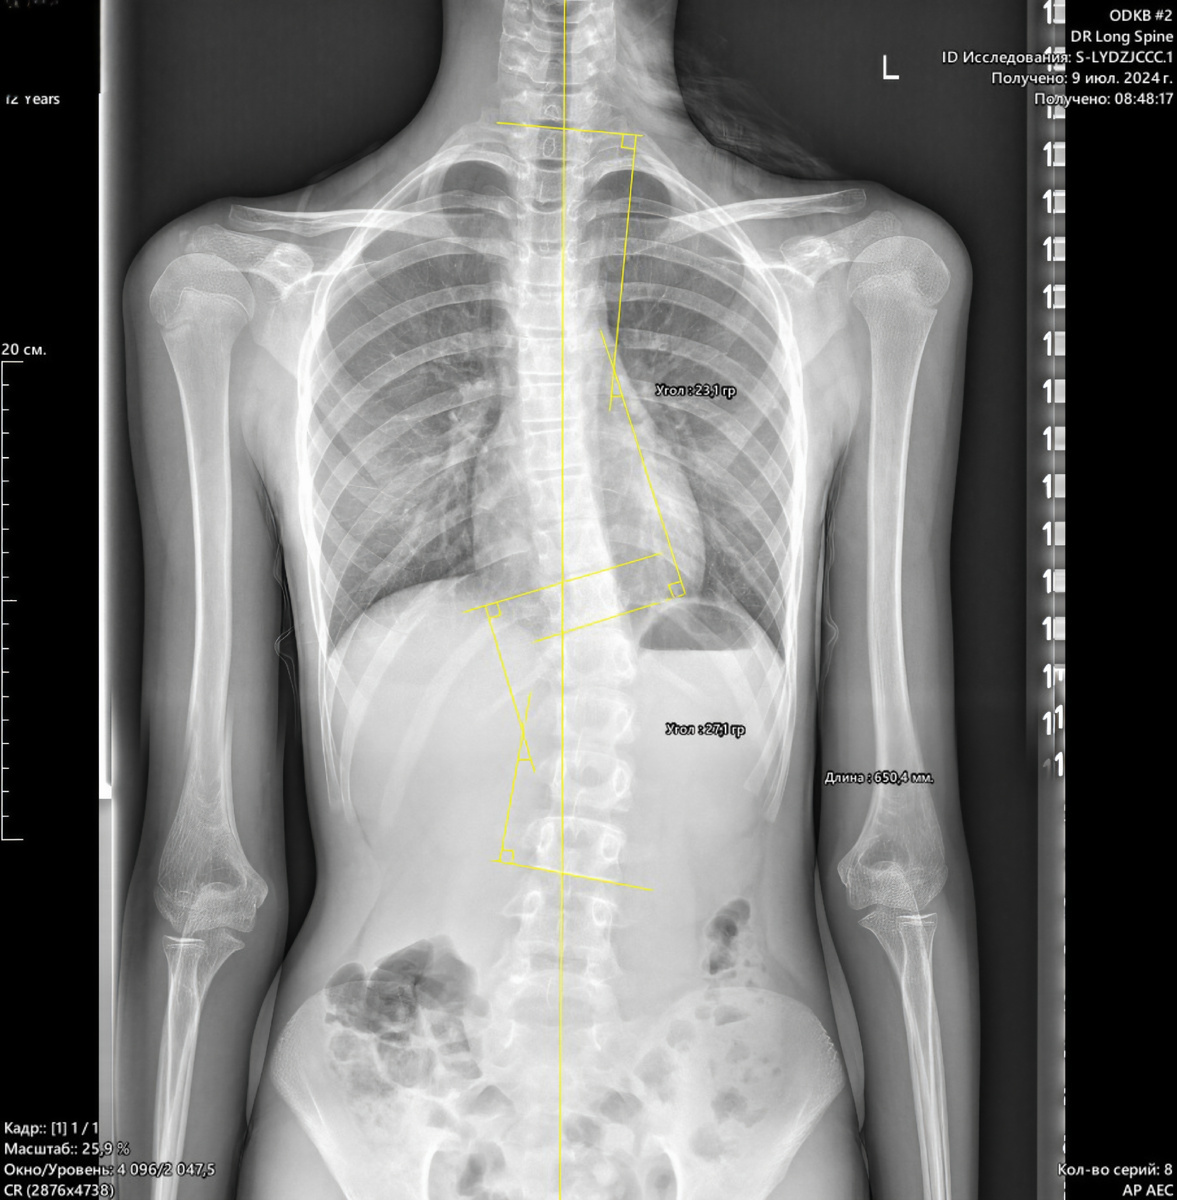

Π’ Π½Π°Ρ‡Π°Π»Π΅ 2024 Π³ΠΎΠ΄Π° ΠΊ Π½Π°ΠΌ ΠΎΠ±Ρ€Π°Ρ‚ΠΈΠ»Π°ΡΡŒ 13-лСтняя Π΄Π΅Π²ΠΎΡ‡ΠΊΠ°. Битуация Π±Ρ‹Π»Π° критичСской: ΠΏΠΎ Ρ€Π΅Π·ΡƒΠ»ΡŒΡ‚Π°Ρ‚Π°ΠΌ обслСдования Π² ΠΏΠΎΠ»ΠΈΠΊΠ»ΠΈΠ½ΠΈΠΊΠ΅ ΠΏΡ€ΠΎΠΈΠ·ΠΎΡˆΠ»Π° рСзкая прогрСссия сколиоза.

На ΠΌΠΎΠΌΠ΅Π½Ρ‚ Π½Π°Ρ‡Π°Π»Π° лСчСния Π΄Π°Π½Π½Ρ‹Π΅ Π±Ρ‹Π»ΠΈ Ρ‚Π°ΠΊΠΈΠΌΠΈ:

β€’ ВСст РиссСра: 0 (Π°ΠΊΡ‚ΠΈΠ²Π½Ρ‹ΠΉ рост!)

β€’ БколиотичСскиС Π΄ΡƒΠ³ΠΈ: ΠŸΡ€Π°Π²ΠΎΡΡ‚ΠΎΡ€ΠΎΠ½Π½ΡΡ грудная 23Β° ΠΈ ЛСвосторонняя поясничная 27Β°.

Π’ΠΠ–ΠΠž! Π£Π³ΠΎΠ» Кобба 27⁰ классифицируСтся ΠΊΠ°ΠΊ III ΡΡ‚Π΅ΠΏΠ΅Π½ΡŒ сколиоза (пограничная ΠΈΠ»ΠΈ Π½Π°Ρ‡Π°Π»ΡŒΠ½Π°Ρ III ΡΡ‚Π΅ΠΏΠ΅Π½ΡŒ), Ρ‡Ρ‚ΠΎ Ρ‚Ρ€Π΅Π±ΠΎΠ²Π°Π»ΠΎ Π½Π΅ΠΌΠ΅Π΄Π»Π΅Π½Π½ΠΎΠ³ΠΎ ΠΈ ΠΎΡ‡Π΅Π½ΡŒ строгого Π²ΠΌΠ΅ΡˆΠ°Ρ‚Π΅Π»ΡŒΡΡ‚Π²Π°.

Π Π΅ΠΊΠΎΠΌΠ΅Π½Π΄Π°Ρ†ΠΈΠΈ: Π‘Ρ‚Ρ€ΠΎΠ³ΠΎΠ΅ ношСниС корсСта Π¨Π΅Π½ΠΎ + СТСднСвная спСциализированная Π¨Ρ€ΠΎΡ‚-гимнастика.